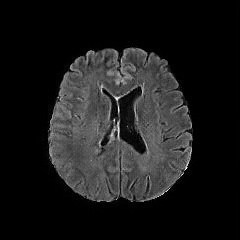

We use two popular medical imaging datasets primarily used for the evaluation of lesion segmentation: the Multimodal Brain Tumor Segmentation Challenge 2018 dataset (BratS18) [21, 2] and the Liver Tumor Segmentation Challenge dataset (LiTS).

BratS18.

The BratS18 dataset provides 210 high grade glioma (HGG) and 75 lower grade glioma (LGG) MRI with binary masks for the tumor (or lack of tumor). Each 3D MRI contains 155 slices of size 240×240240240240\times 240. Not every slice contains a tumor, and therefore healthy MRI are provided by this data as well. We use the FLAIR modality image for all the experiments because the entire tumor is represented well by this modality.However, we also show more experimental results on other modalities, where the ANT-GAN provides impressive visual quality. A more detailed medical description of the data can be found on the challenge website.111https://www.med.upenn.edu/sbia/brats2018.html

Aside from the difference in imaging tissue and modality of these two data sets, the tumor regions on the CT images are of different shape and size, as can be seen in Figure 4. Also, many CT scans are acquired in a way that introduces greater noise-like artifacts than MRI. For each dataset, 80%percent8080\% of randomly selected data are used for training and the resting 20%percent2020\% for testing.